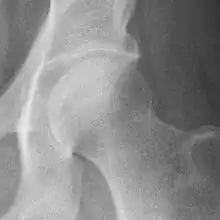

Hip joint with no signs of osteoarthritis.

The most commonly used radiographic classification system for osteoarthritis of the hip joint is the Kellgren–Lawrence system (or KL system).[6] It uses plain radiographs.